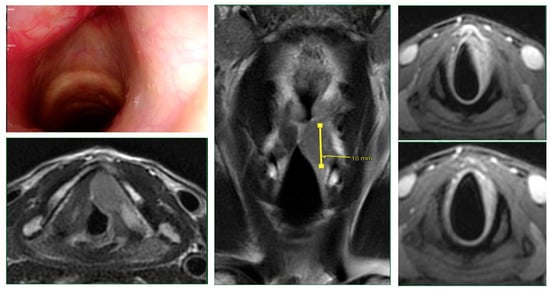

Intraoperative endoscopy allowed for a thorough reassessment of the tumor extension and highlighted some clinical-endoscopic elements of suspected initial extra laryngeal extension (Figure 1 and Figure 2).

Figure 2. The radiological finding of suspected extra laryngeal extension through the cricothyroid membrane is evidenced (yellow arrow). Intraoperative evaluation (yellow arrow) confirmed the extra laryngeal spread through a vascular foramen of the cricothyroid membrane.